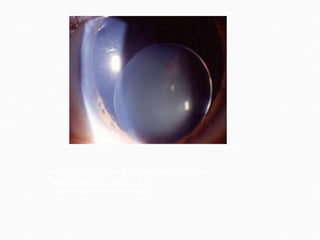

It is one of the most dramatic and serious complications of cataract surgery. Usually occurs in hypertensives and patients with arteriosclerotic changes. May occur during operation or during immediate postoperative period.

webeye.ophth.uiowa.edu  ophthalmicphotography.info

It is  characterised  by spontaneous gaping of the wound followed by expulsion of the lens, vitreous, retina, uvea and finally a gush of bright red blood. Although  treatment  is unsatisfactory, the surgeon should attempt to drain subchoroidal blood by performing an equatorial sclerotomy. Most of the time eye is lost and so evisceration operation has to be performed.